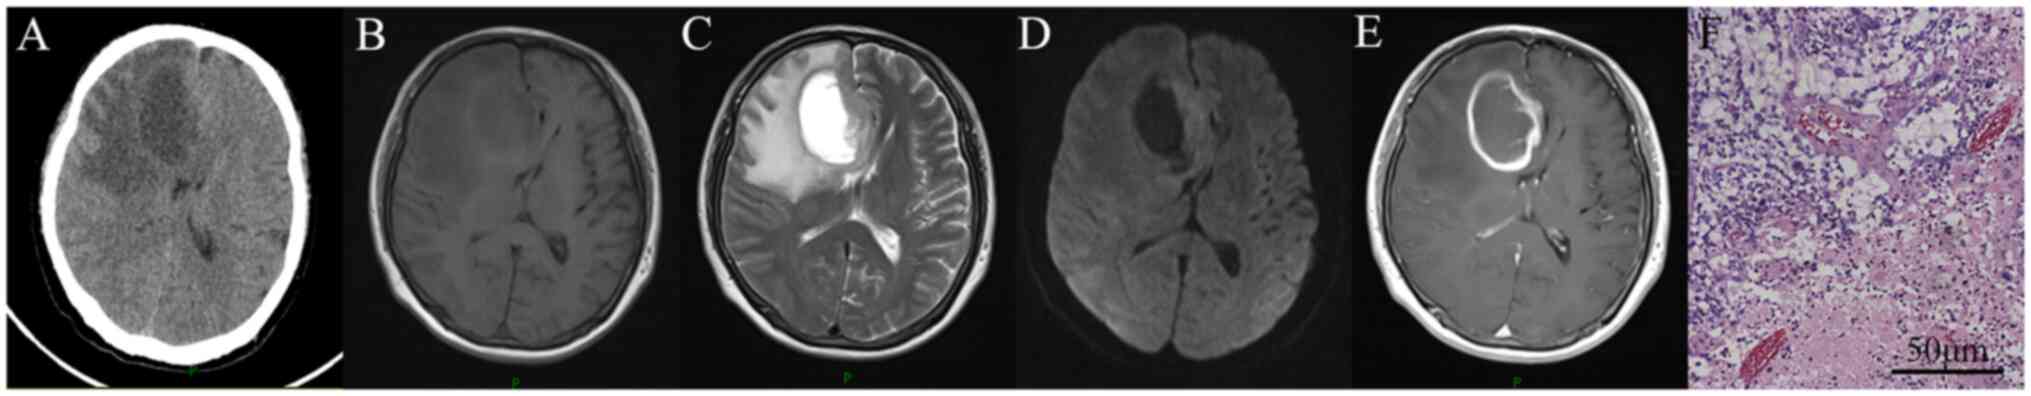

The 10 HIV-positive patients with glioma who were enrolled in the present study comprised 5 patients with GBM, 2 patients with anaplastic astrocytomas (AAs), 2 patients with anaplastic oligodendrogliomas and 1 case of astrocytoma. These patients represented 2.8% (10/3,631) of all patients infected with HIV, 12.5% (10/80) of all patients with HIV-associated focal mass lesions and 3.4% (10/294) of all patients with cerebral gliomas at the Department of Neurosurgery of Beijing Ditan Hospital. At the time of diagnosis, the patients comprised 9 men and 1 woman with a mean age of 36.7 years (range, 23-57 years). Seizures were reported by 4 patients at their initial presentation. The others presented with intracranial hypertension, limb hemiplegia or aphasia. All the brain lesions were supratentorial, with the majority located in the cerebral hemisphere, and only one in the paraventricular region and two at the basal ganglia. Lymphocyte profiles were available for all the patients. The median CD4+ T-cell count and HIV load at glioma presentation were 441 cells/µl (range, 96-925 cells/µl) and 10 copies/ml (range, 0-9,704 copies/ml), respectively. None of the patients had any pre-existing systemic tumors or had developed AIDS-defining diseases, such as Kaposi's sarcoma, PCNSL, TE or PML. In a number of these cases, the intracranial tumors were detected several years after HIV diagnosis, with an interval ranging from 50 days to 10 years, with a median of 4 years. All the patients received regular HAART treatment after the detection of HIV, with the exception of one who privately withdrew from the use of drugs after 2 years of regular medication and had a high HIV load of 9,704 copies/ml at glioma detection. The radiological and pathological images of the patients appeared consistent with immunocompetent glioma (Fig. 1). The treatments received included SR, SB, RT and CTh, which differed from the standard algorithm for AIDS-defining diseases, such as the treatment of Toxoplasma gondii for TE and high-dose methotrexate-based chemotherapy for PCNSL. The therapeutic regimens of RT and CTh were applied according to the guidelines of the Chinese Glioma Cooperative Group, Society for Neuro-Oncology of China and Chinese Brain Cancer Association, and varied by taking into consideration the tumor grade, patient age, performance status and tumor molecular features (7). At the time of follow-up, half of the patients had died due to tumor progression. The median survival time was 7.5 months after tumor diagnosis. Patient characteristics, management and outcomes are summarized in Table I.

Figure 1

Radiological and pathological images of a 53-year-old male patient with human immunodeficiency virus and glioblastoma multiforme. (A) Computed tomography, (B) MRI-T1-WI, (C) MRI-T2-WI, (D) diffusion-WI and (E) contrast-enhanced T1-WI. (F) Hematoxylin and eosin staining. MRI, magnetic resonance imaging; WI, weighted imaging.